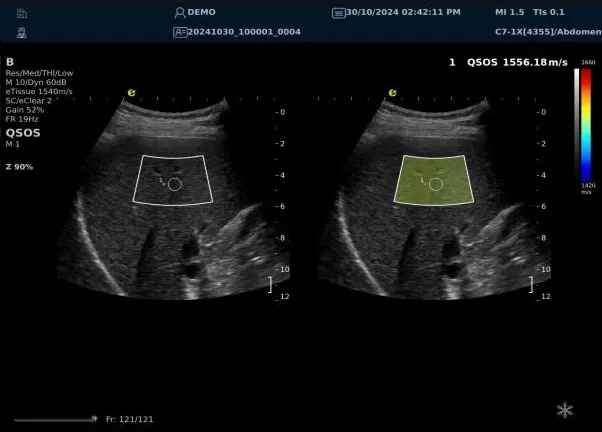

640.jpg123 (2).jpg可以设想,单位时间可发射的脉冲波越多、单位面积可发射的脉冲波越密集,得到的数据结果就越快、越多。也就是说,如果医生希望得到实时、大幅的声速定量图像,就需要超声系统具备“超快速”发射和接收的能力,hjc888黄金城官网医疗(ESI)ePascal东风系列超声平台的200+倍成像速度,成为了这项新技术得以临床应用的重要条件。

以上为应用声速定量成像技术检查肝脏的超声图像,图中在取样框内选择了三个测量区域,得出了各区域内的组织声速值以及声速衰减系数等结果。